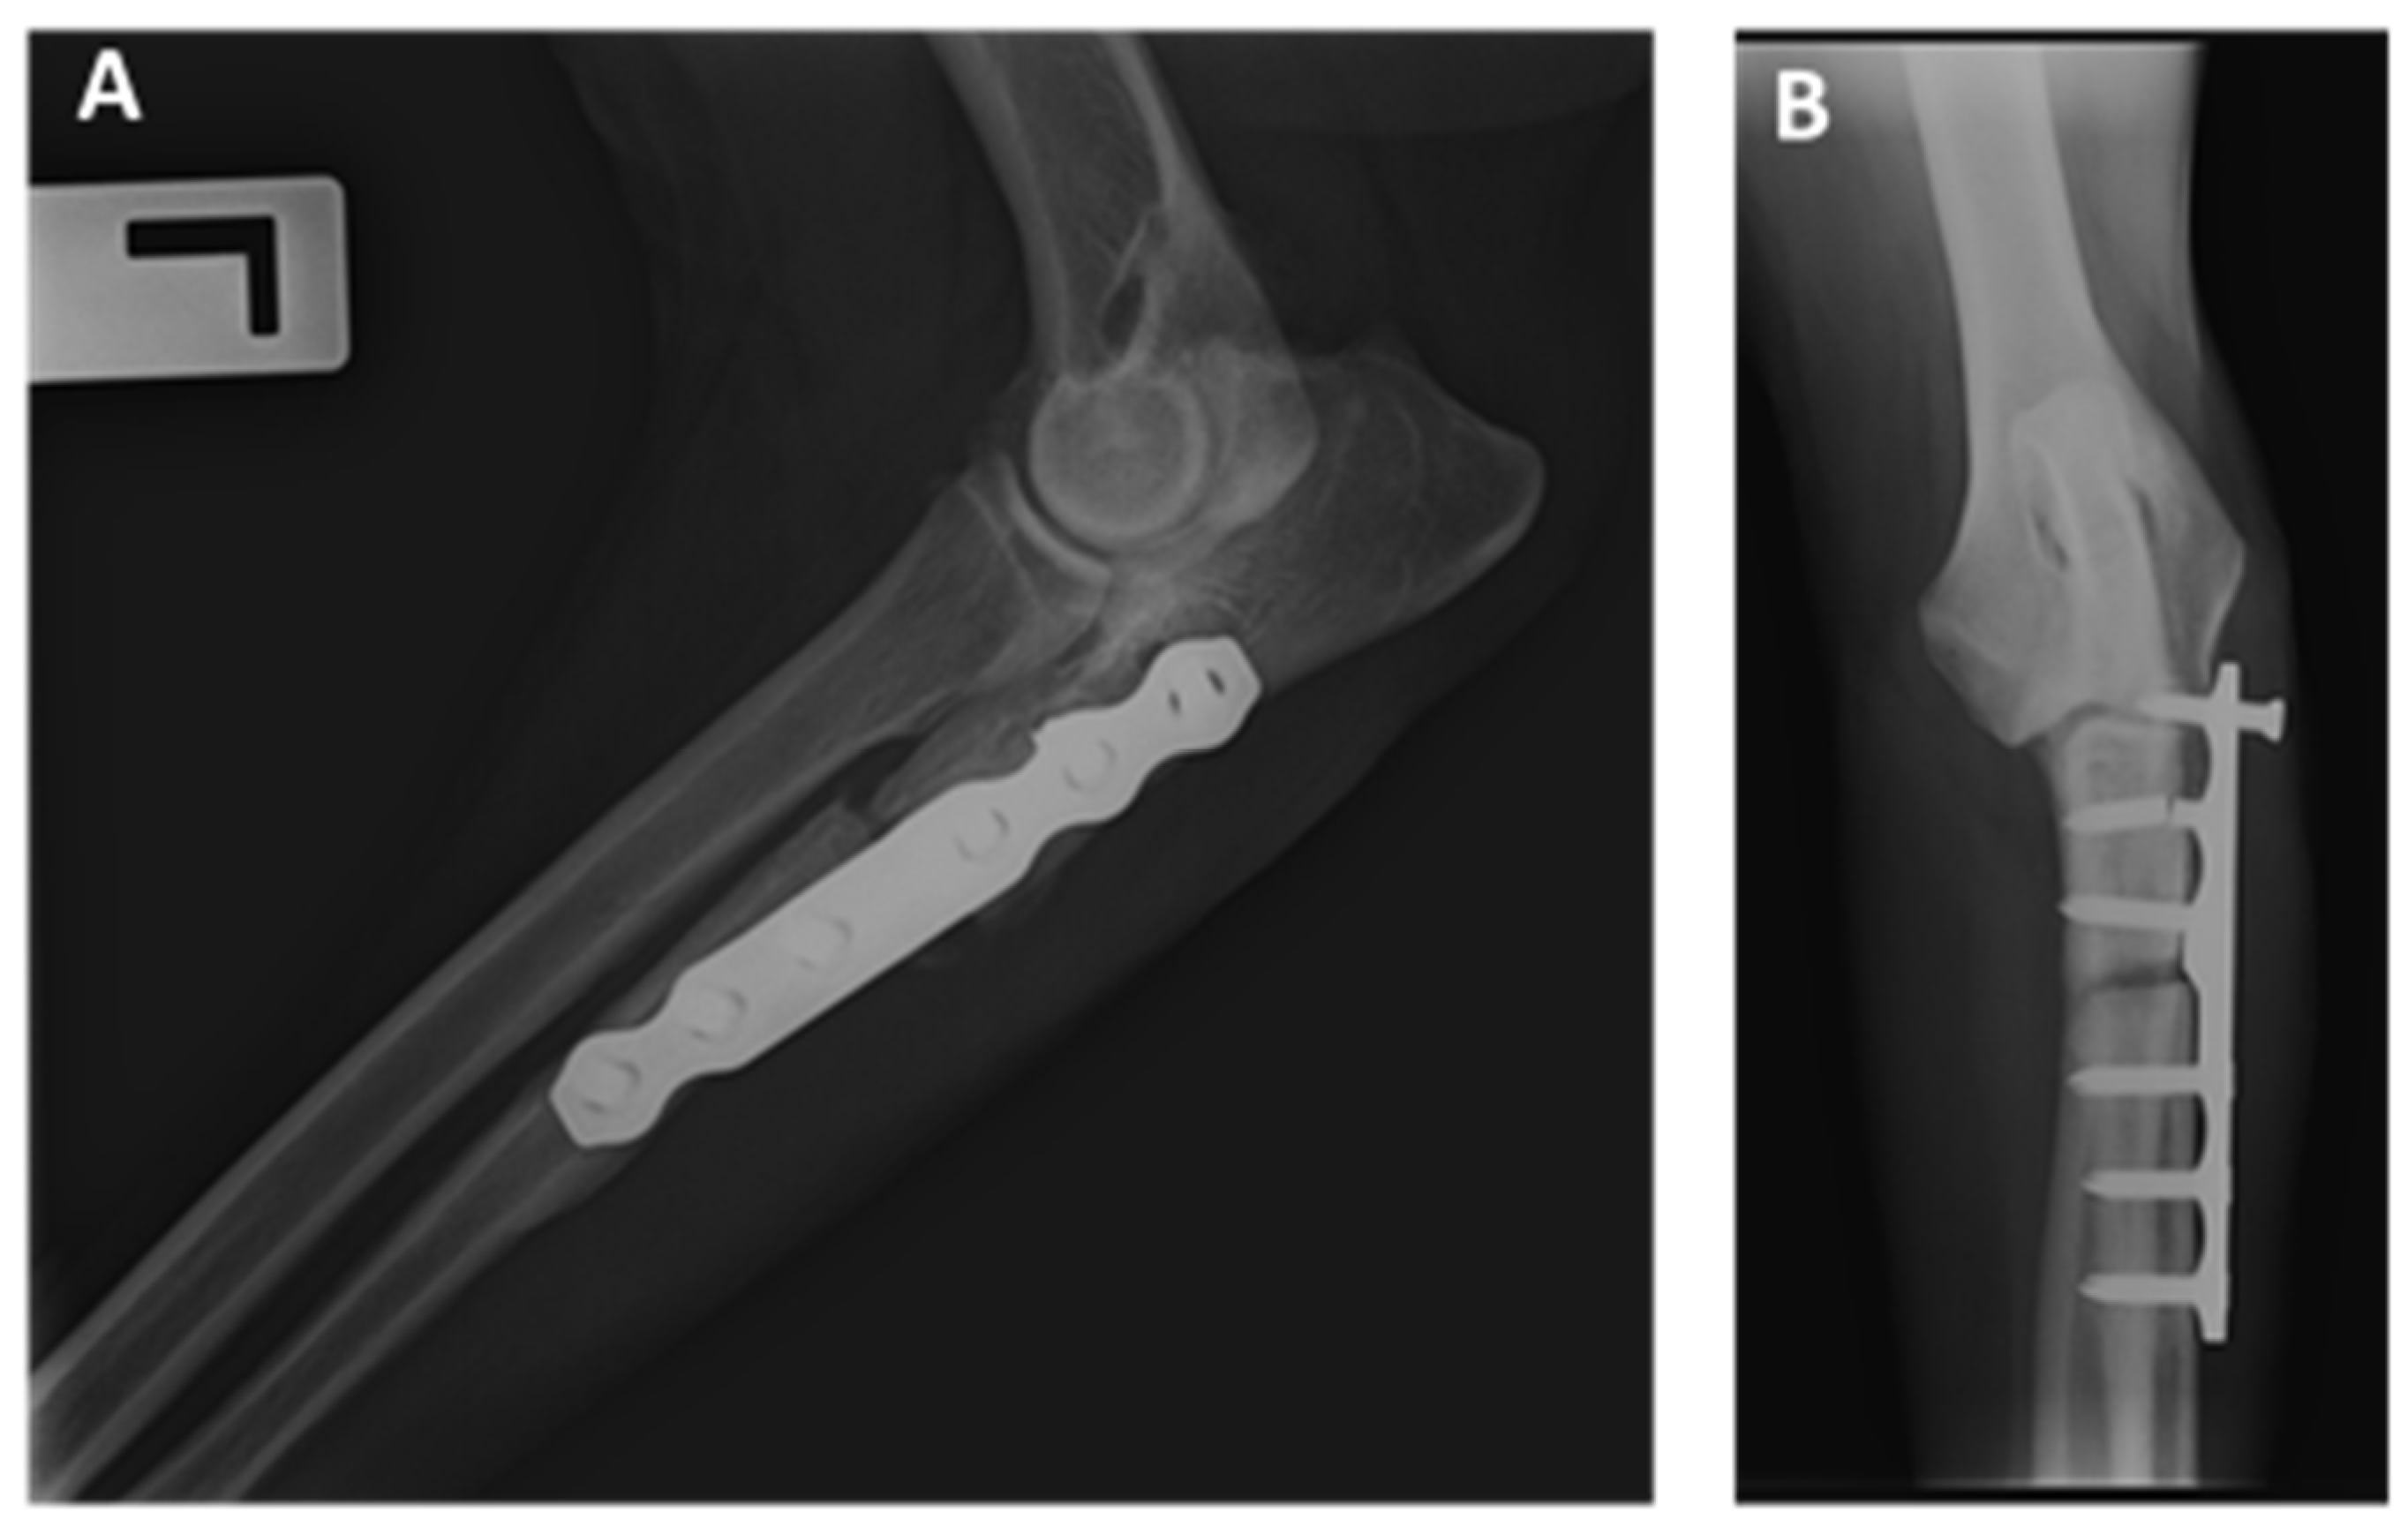

Abstract

2.2. Surgical Procedure

3.3. Radiographic Outcomes

3.4. Minor and Major Complications